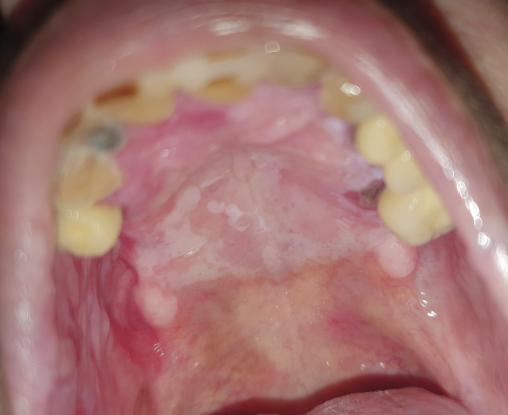

Marie-Catherine, 78 ans, consulte car elle a la sensation d’avoir un corps étranger au niveau du palais.

L’examen clinique révèle des plages papuleuses de couleur blanche (figure ). Une biopsie est effectuée, confirmant le diagnostic de lichen plan hypertrophique.

Forme la plus rare, le lichen plan hypertrophique est secondaire à une réaction de régénération épithéliale.

Des lésions papuleuses hyperkératosiques à aspect pavimenteux avec des variations d’épaisseur sont observées. Des plages hyperkératosiques séparées par une muqueuse normale peuvent être également visibles.